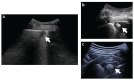

Pulmonary infarction (PI) is a possible consequence of pulmonary embolism (PE). The real incidence of PI could be underestimated considering only non-fatal PE presentation. However, following postmortem examination, the prevalence of PI is considerably higher. This evidence suggests the necessity of proper diagnostic protocol for identifying PI. Unfortunately, PI diagnosis can sometimes be challenging, due to the overlapping of symptoms with other diseases. Nowadays, the diagnosis is mainly based on radiological evaluation, although the combination with emerging imaging techniques such as ultrasound and nuclear scanning might improve the diagnostic algorithm for PI. This review aims to summarize the available data on the prevalence of PI, the main predisposing factors for the development of PI among patients with PE, to resume the possible diagnostic tools, and finally the clinical and prognostic implications.